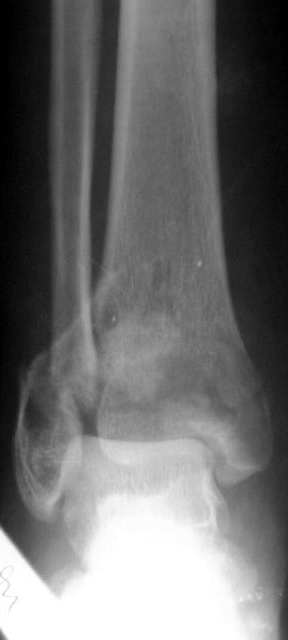

Перелом 43С

Поступил больной 57 лет 14.06.04 в наше отделение.Простой перелом малоберцовой кости Взрывной перелом дистальных отделов болыпеберцовой кости,

Вколоченный перелом дистальных отделов большеберцовойкости.Проводим репозицию с помощью скелетного вытяжения, перед операцией. Думаем как собрать б/б кость? Какой доступ использовать? Может сразупервичный артродез?Как то в форуме говорилось о доступе через м/б кость для артродеза. Возможноли его использовать в данном случае?Если кто-то его использует, может поделится информацией, как правильно егоделать?Сергей ЗыряновНСО г Куйбышев.ЦРБ